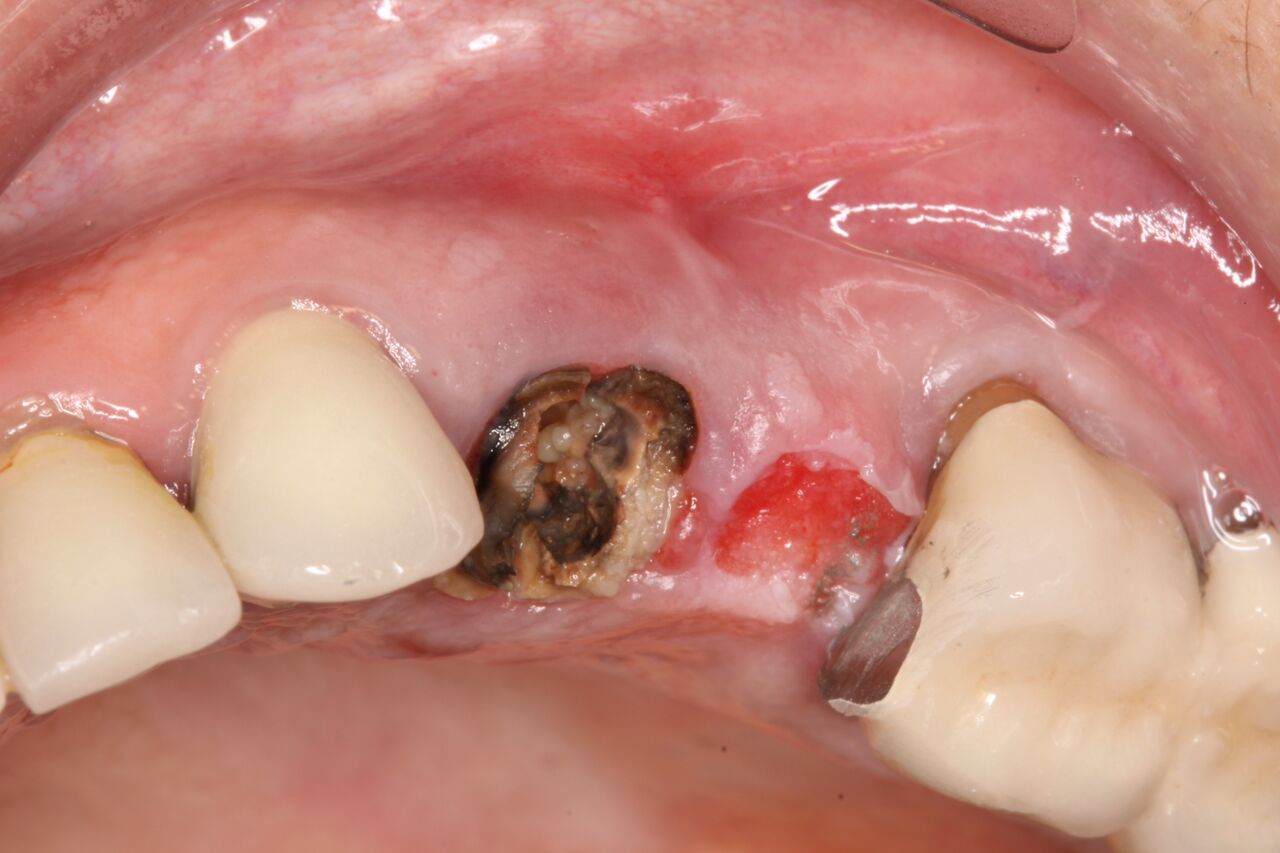

Case Example 2

A 67-year-old woman presented on an emergency basis with a bad odor and taste from crown No. 12, which had been diagnosed that day at hygiene recall as decayed and no longer attached to the underlying root (Figure 8 and Figure 9). The patient was anesthetized and the existing bridge was sectioned (Figure 10), leaving crown No. 14 intact. The No. 12 root was extracted and the site was fully debrided of granuloma. A platform shift implant was stabilized in excess of 45 Ncm in position No. 12, which was prosthetically correct. The soft tissue of pontic site No. 13 was contoured to mimic soft tissue contours of a bicuspid and an implant was secured in excess of 45 Ncm. Implant No. 13 was milled to allow for unimpeded seating of the temporization abutment, whereas implant No. 12 did not need milling as it was a platform-shift implant. The existing crown No. 12 and cantilever No. 13 were revised to be a temporary bridge on Nos. 12 and 13 (Figure 11 and Figure 12). The revised temporary bridge was positioned in infraocclusion and cemented after the extrusion of excess cement extraorally (Figure 13). No bone graft or sutures were placed as the temporary crowns sealed the sockets.

(10.) Initial clinical evaluation of Nos. 12 through 14 after crown on No. 12 and pontic on No. 13 removed.

Figure 10

(11.) Extraction of fractured and decayed No. 12 with periapical granuloma and original

Figure 11

(12.) Extraction of fractured and decayed No. 12 with periapical granuloma and original

Figure 12